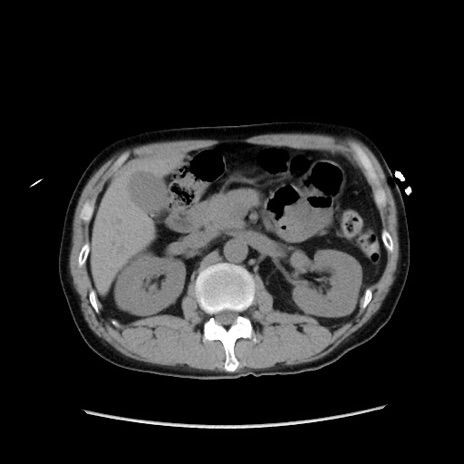

症例37(横断像)

【症例】40歳代 男性

【主訴】腹痛

【現病歴】4時間ほど前に電車に乗車中に臍部上より腹痛出現。徐々に増悪し起立困難となり、救急外来受診。生ものは数日食べていない。今朝お雑煮を食べた。

【身体所見】BT 36.8℃、BP 117/84mmHg、HR 91/min、SpO2 97%、苦悶様、腹部:臍上部広範囲圧痛あり、反跳痛±

【データ】WBC 8100、CRP 0.03